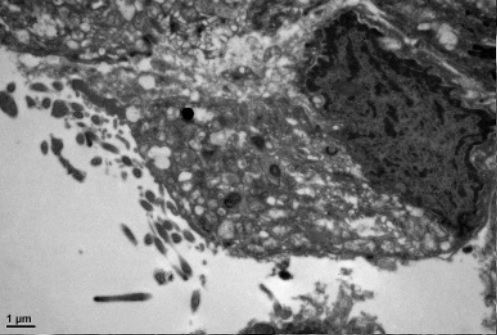

部分超微病理电镜图示例:

图4 A 正常气管纤毛

图4B 气管粘膜纤毛先天发育不良(纤毛不动症)